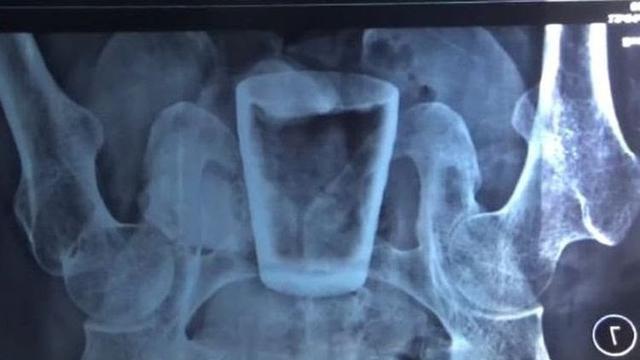

Liputan6.com, Jember - Nurlasiadi, pria Dusun Rowo Tengu, Desa Sidomulyo, Kecamatan Semboro, Jember, mengaku mengalami sakit nyeri pada bagian perut, 3 bulan terakhir. Usut punya usut ternyata ada gelas kaca utuh di dalam tubuhnya.

Pria berusia 35 tahun itu pun langsung dilarikan ke RSUD Balung. Gelas kaca utuh berukuran 8 sentimeter tersebut kemudian diketahui berada di bagian rektum, atau dekat lubang dubur setelah Nurlasiadi menjalani CT Scan.

"Dari hasil CT Scan dan didapati foto rontgen memang tampak seperti di perut. Tapi tepatnya berada di dalam rektum anus (dekat lubang dubur), benda asing (gelas) itu," kata Kepala Humas RSD Balung dr Doddy Radi Sakti, Kamis (7/4/2022).

Doddy menjelaskan, Dari hasil diagnosa secara medis, gelas kaca tersebut dimungkinkan berada di dalam perut pasien, dengan dimasukkan lewat lubang dubur. Beruntuk pihak rumah sakit bisa dengan mudah mengeluarkan gelas tersebut.

"Karena posisi benda asing yang ternyata gelas itu berada dekat dengan dubur. Makanya dilakukan dengan robekan kecil untuk mengambil gelasnya. Bukan operasi bedah di perut," ucapnya.